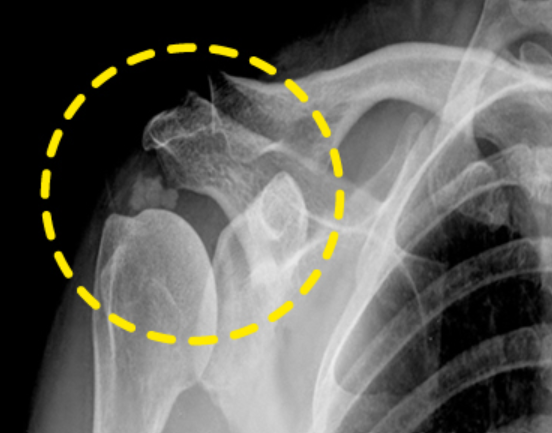

어깨통증 원인 4. 석회성 건염

어깨통증 원인 네 번째는 석회성 건염입니다. 석회성 건염 역시 지속적인 통증보다는 갑작스럽게 어깨 부위에 심한 통증이 느껴질 때 의심할 수 있습니다. 이 때는 밤잠을 이룰 수 없을 정도로 고통을 주는데 보통 노화나 순환 장애로 어깨 부위 특히 힘줄에 칼슘이 축적되며 힘줄과 주변 조직에 통증을 유발하게 됩니다. 질병의 증상은 다양한데 해당 부위를 누르는 경우 심한 통증이 느껴진다면 우선적으로 석회성 건염일 가능성이 높으며 이때도 초음파 촬영이나 X레이 검사를 실시합니다.

석회성 건염 치료는 증상이 심하지 않으면 약물이나 주사치료, 냉·온찜질, 물리치료(체외충격파) 등 비수술적 치료를 우선적으로 실시하며 이러한 방식으로도 통증이 완화되지 않는다면 석회를 제거하는 관절경 수술을 동반합니다. 따라서 여러 이유로 발생하는 어깨통증 원인에 대해 이해를 하시고 가까운 전문병원을 찾아 진단을 받으신 후 증상에 맞는 치료를 받으시기 바랍니다.